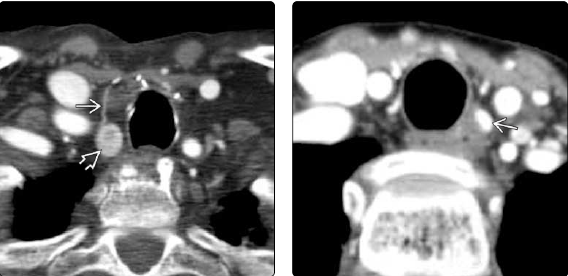

9. Fig. 8. a - CT axial section with contrast, formation (thin arrow) behind the left lobe of the thyroid gland (thick arrow) in the tracheoesophageal sulcus, slightly less contacted in the delayed image; b - sagittal section, heterogeneous oval formation (thin arrows) behind the left lobe of the thyroid gland (thick arrow) (images from Diagnostic Imaging: head and neck, 3rd edition, Elsevier 2017). | |

| Subject | ||

| Type | Other | |

View

(144KB)

|

Indexing metadata ▾ | |